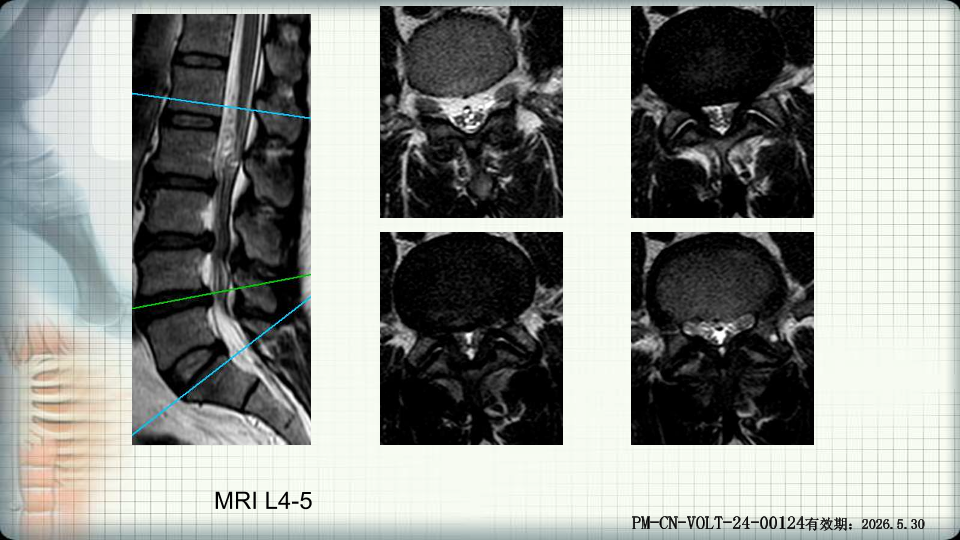

管狭窄症非手术治疗-谢学虎